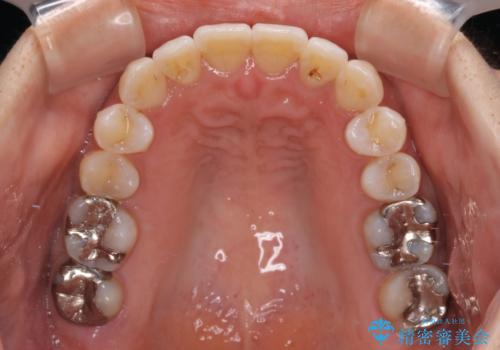

- 上顎の八重歯と全体的なデコボコを気にして来院された患者様です。

口元の突出感はなかったため非抜歯矯正での対応となりますが、八重歯を改善する際に上顎前歯が前突する可能性があったため、上顎臼歯部にアンカースクリューを使用して、歯列が前方に転位しないようにすることとしました。

また舌のトレーニングを行うことで、上顎前歯の突出予防や上下前歯に隙間ができなくなるようにしました。